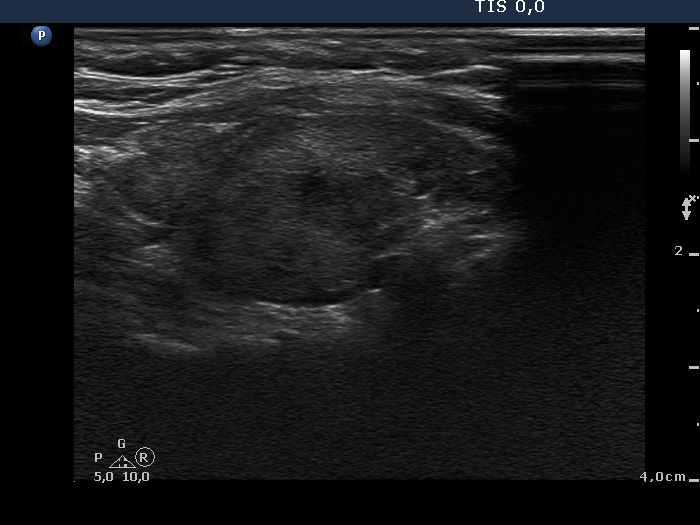

Third examination 18 months after initial examination (third row):

Clinical data: Another relapse of hyperthyroidism occurred 3 months ago. Thereafter, the dose of thyrostatic was increased.

Palpation: unchanged.

Result of blood test: subclinical hyperthyroidism (TSH 0.03 mIU/L, FT4 18.1 pM/L).

Ultrasonography: The pattern was the same.